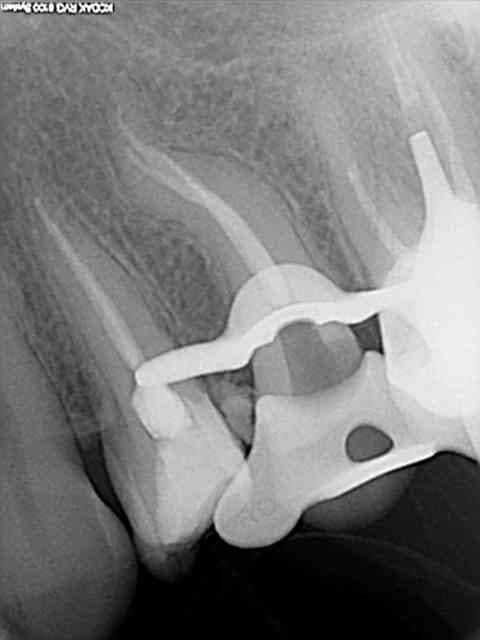

Une des premières fois que j'ai utilisé un contre-angle avec localisateur intégré.

Je me suis cru à l'abri avec le contrôle du torque sur l'instrument en temps réel.

Les diodes se sont alummées au début de la descente dans le canal et j'ai voulu continuer à avancer avec l'instrument en rotation malgré un cathétérisme manuel pas réalisé sur la totalité du canal.

Fracture , puis initiation de fausse route en essayant de passer à coté manuellement.